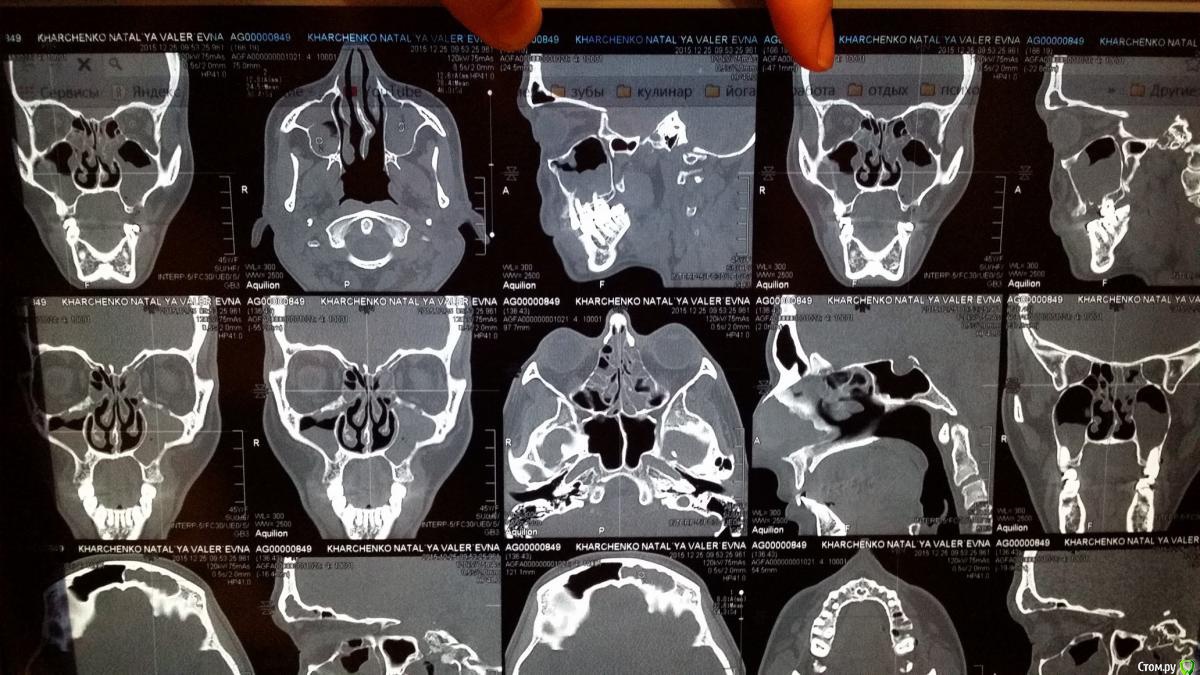

natali777 Опубликовано 6 января, 2016 Автор Поделиться Опубликовано 6 января, 2016 кт на 5 день после удаления Ссылка на комментарий

natali777 Опубликовано 6 января, 2016 Автор Поделиться Опубликовано 6 января, 2016 кт ппн после удаления 5 и 6 зубов Ссылка на комментарий